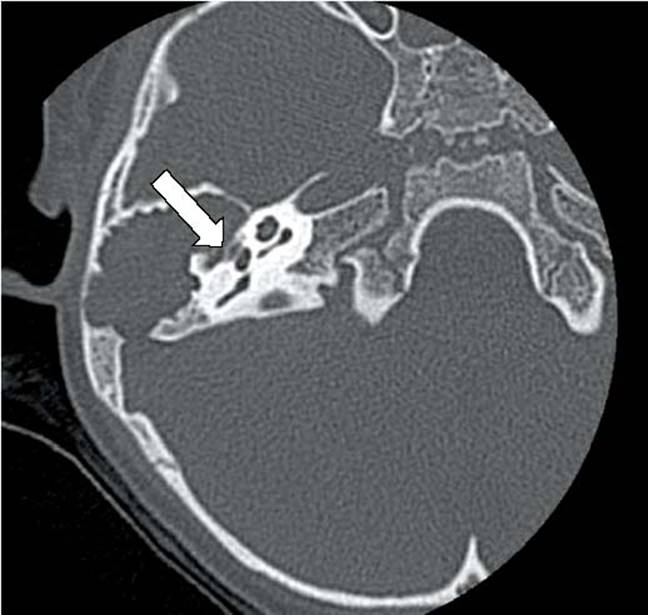

Computed tomography (CT) is the study of choice to examine the temporal portion of the facial nerve, allowing assessment of the facial nerve in the fallopian canal from the IAC to the stylomastoid foramen. CT should be obtained for facial palsy associated with temporal bone fractures or with middle-ear diseases such as chronic otitis media/mastoiditis or cholesteatoma (Fig. 5.4).

Figure 5.4 Computed tomographic image in the axial plane of a 3-year-old child with a large cholesteatoma that fills the mastoid and middle ear and has eroded the fallopian canal in the tympanic segment of cranial nerve VII. Arrow points to the tympanic segment.